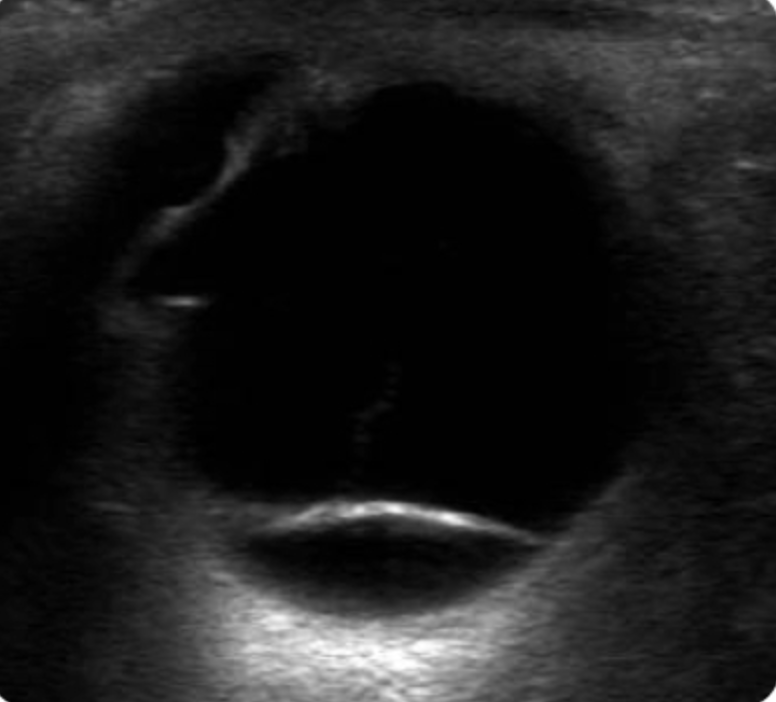

what is this showing

A

fluid behind the retina

discrete hyperechoic retina line

retinal detachment